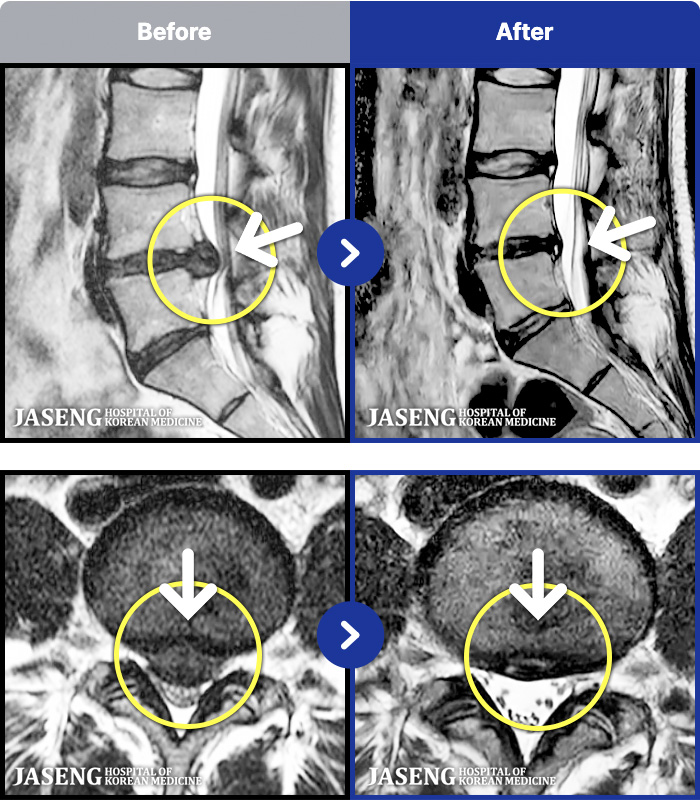

- MRI ġ

MRI ġ

1,301 MRI ũ ʸ Ȯϼ.